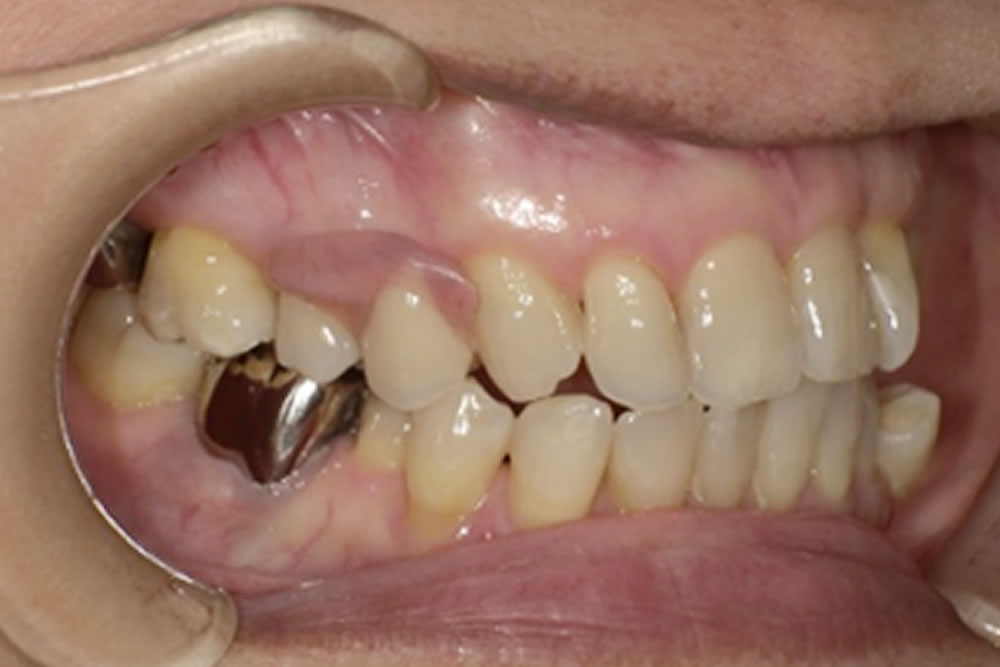

こちらの方は、当院が運営する「入れ歯相談サイト」をご覧になり、無料相談を通じて来院されました。右上の欠損部分をどの治療法で補うべきか検討されており、インプラント・ブリッジ・入れ歯の3種類の治療法について、それぞれの特徴やメリット・デメリットを知りたいというご希望がありました。

これらの点を踏まえ、最終的に選ばれたのがミラクルデンチャーでした。外科的処置を伴わず、歯を削ることもなく欠損部を補えること、そして審美性が高いこと、清掃がしやすいことなどが主な理由です。ミラクルデンチャーは特殊な「キーとロック」に似た構造によって高い維持力を発揮するため、最初は取り外しに少しコツが必要ですが、慣れると外れにくく快適に使用できるという特徴があります。